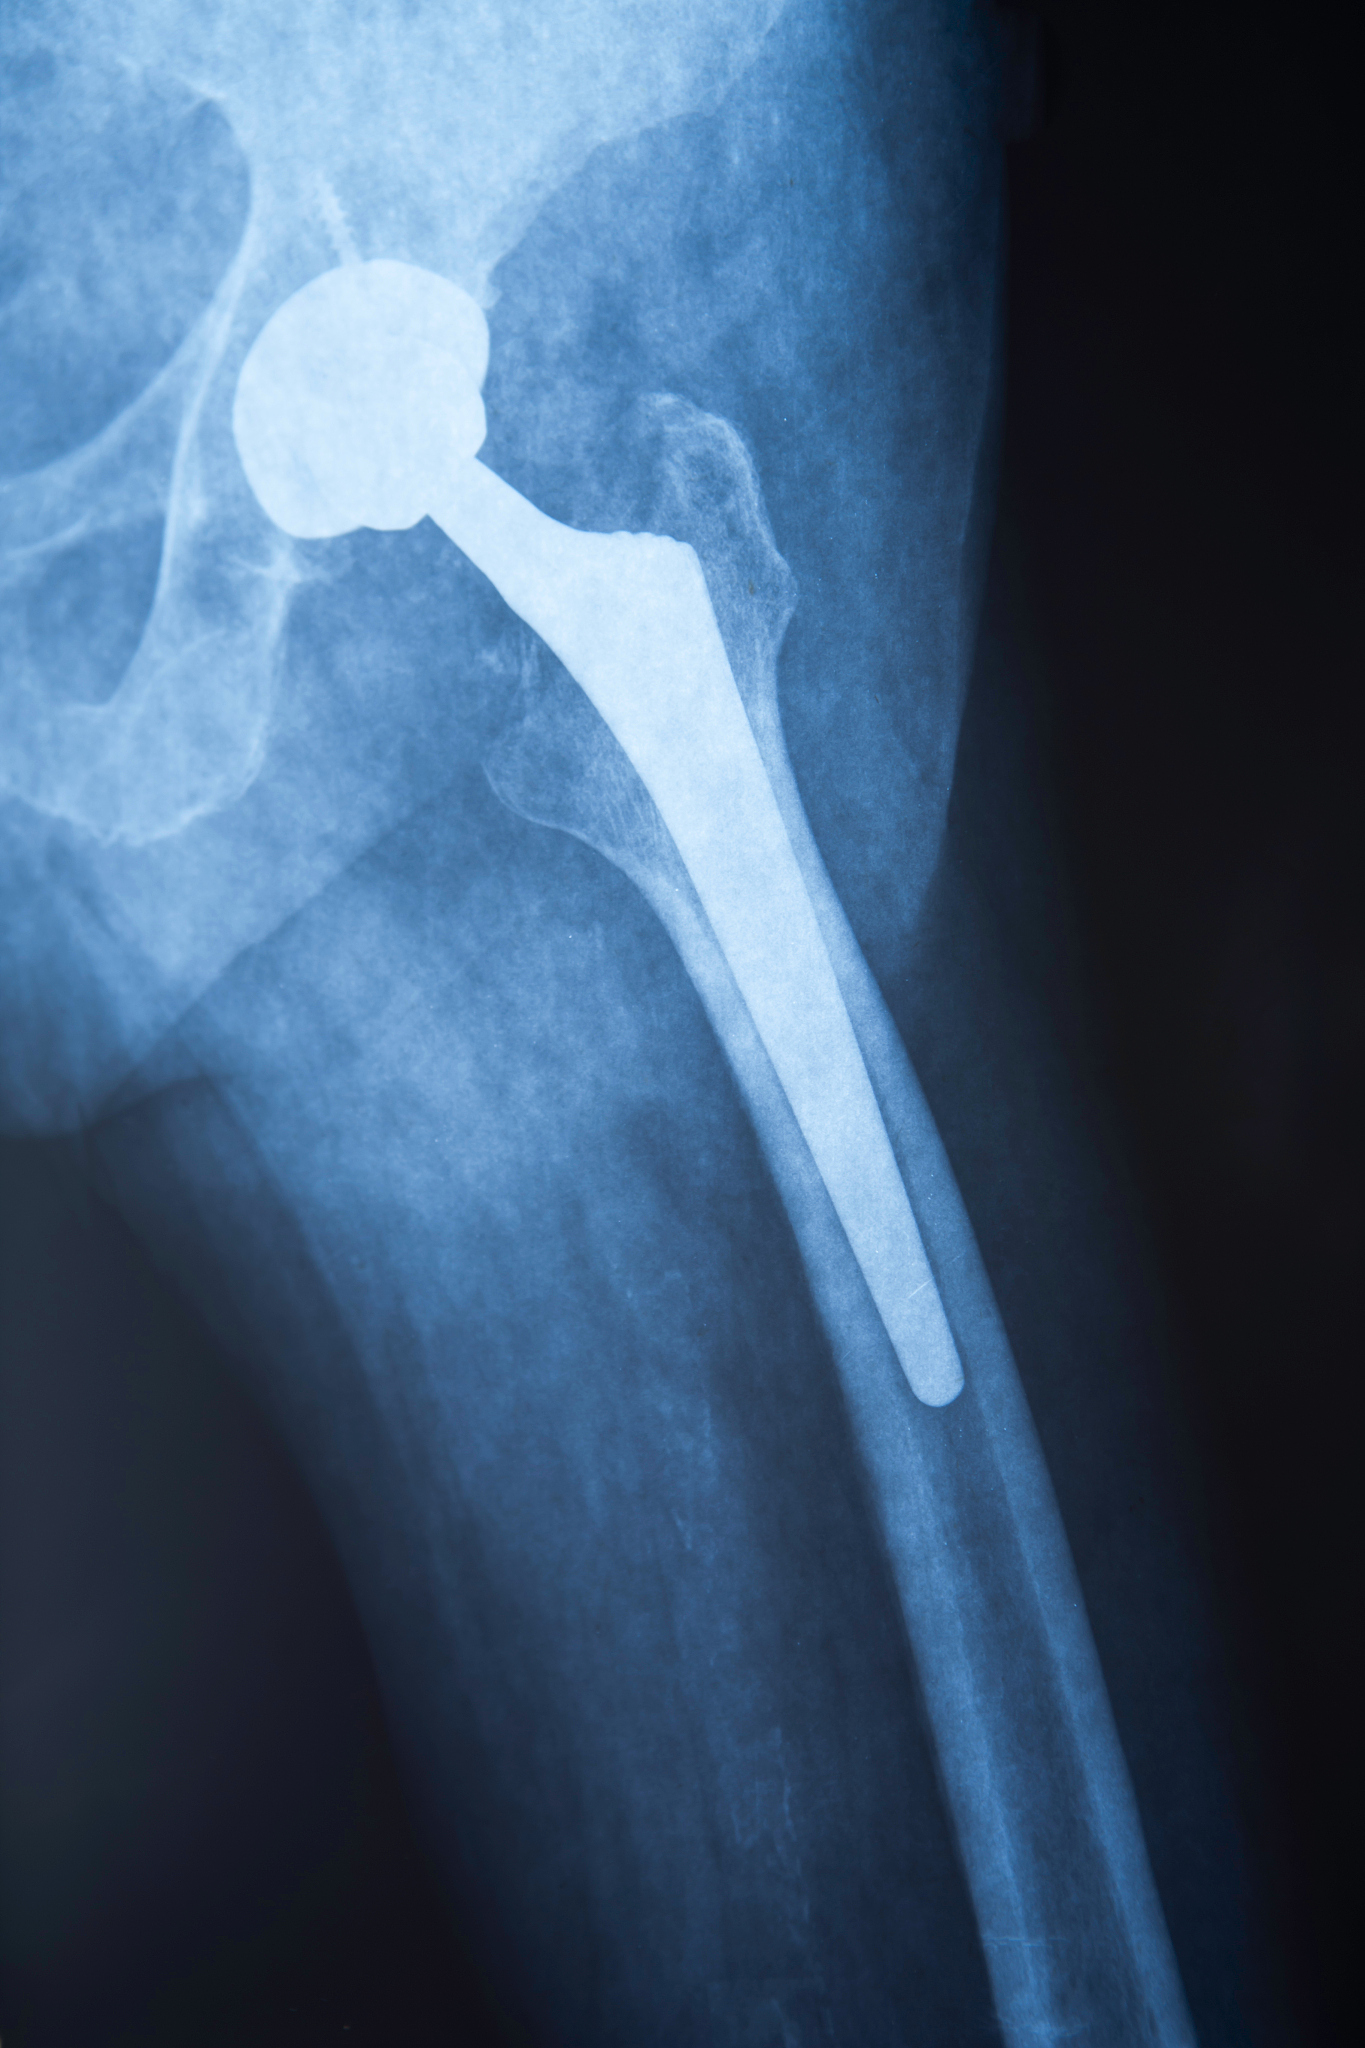

是的,我对激素性股骨头坏死(Avascular Necrosis of the Femoral Head, ANFH)有所了解。ANFH是一种髋关节疾病,也被称为髋关节坏死。它通常由股骨头血液供应不足引起,导致骨组织死亡和坏死。

ANFH的症状可能包括髋关节疼痛、活动受限、步态异常等。早期诊断和治疗非常重要,以避免病情进展并减少骨关节损伤。治疗方法可以包括限制活动、减轻关节负重、物理治疗、药物治疗、手术等,具体方案因个体情况而异。